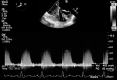

Tetralogy of Fallot (TOF) is a heterogeneous congenital heart disease that is occasionally diagnosed during adulthood. However, although they are often asymptomatic, adult patients with uncorrected TOF often have a poor prognosis. Poor outcomes indicate the importance of the identification and management of these patients, especially in the context of intercurrent disease or noncardiac surgery. We describe a case of clinically silent TOF in a 51-year-old woman. TOF was unmasked during a major noncardiac surgery for a polytrauma and successfully treated with the cooperation of a multidisciplinary team. (Level of Difficulty: Advanced.).